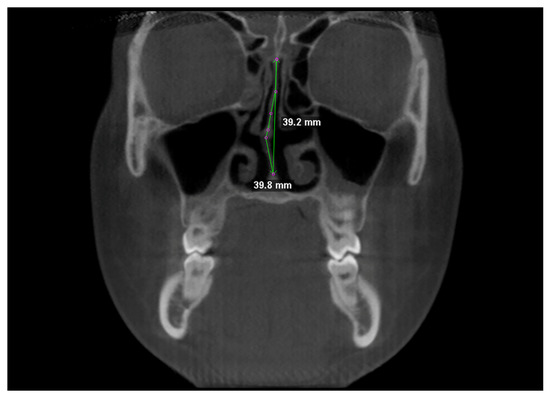

2.3. Assessment of Nasal Septum Deviation (NSD)

Nasal septum was traced at two different levels in coronal view, i.e., at the Crista Galli, and (2) at the Anterior Nasal Spine (Figure 3). Tracing was performed in the cranio-caudal direction by placing points 1–2 mm apart [1]. NSD was calculated according to the “degree of tortuosity” or the ratio of length of the curve to the length of an imaginary line in the mid sagittal plane [1], expressed with the formula:

TR = L   actual L   ideal

Both the actual length of the septum and its ideal length were used to calculate TR values [26].

Figure 3. Linear measurements for calculating the tortuosity ratio (TR).